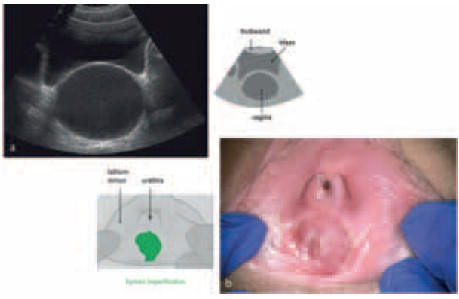

Hymen imperforatus

In de huisartsenpraktijk is hymen imperforatus een zeldzame oorzaak van primaire amenorroe. Een goede anamnese en lichamelijk onderzoek kunnen leiden tot de juiste diagnose. De patiënte die wij in deze casus bespreken is een klassiek voorbeeld van deze aangeboren aandoening.